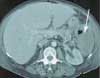

Figure 1

A CT scan reveals complete liquefaction necrosis of the spleen and a few air bubbles within the fluid collection (Figure 1). Upper endoscopy shows a large, 5-cm, confluent ulcer bed on the proximal greater curvature of the stomach that extends to the fundus (Figure 2). Biopsy results demonstrate fundic-type gastric mucosa with marked acute inflammation, necroinflammatory debris, and granulation tissue--all consistent with an ulcer (Figure 3). Histologic findings are negative for Helicobacter pylori.